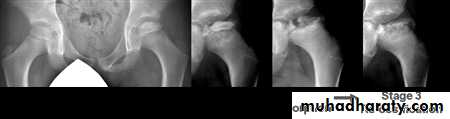

Pathological process take 2-4 years to complete .

Stage 1.. Ischemia and bone death .

Stage 2.. Revascularization and repair .

Stage 3.. Distortion and remodeling .

X-ray

1- at the beginning the x- ray look normal some time we can see asymmetry of the ossific centers ; bone scan is helpful at this stage (showing the avascular area) .

2- later on the increase density of the ossific nucleus will be clear ; and there is increase in the joint space .

3- fragmentation of the epiphysis .

4- flattening and lateral displacement of the epiphysis .5- widening of the metaphysis .

6- in sever and advance cases the head become mushroom shape .